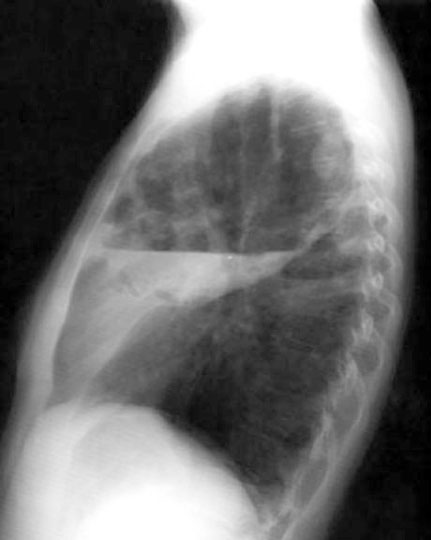

Case 4

Lateral

Labeled Image

What are the contents of a cavity?